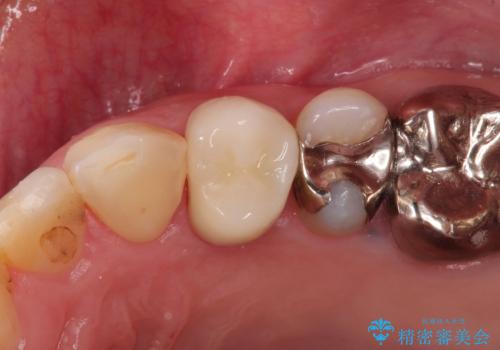

セラミックインレー 天然の歯に近い透明感や色調を再現する

- 銀の詰め物がとれたことを主訴に来院された患者様です。

むし歯を除去しセラミックインレーにて修復を行いました。

セラミックインレーは天然の歯に近い透明感や色調を再現することが可能です。治療では自然な見た目になるまで追及しますので患者さんには非常に満足していただけました。